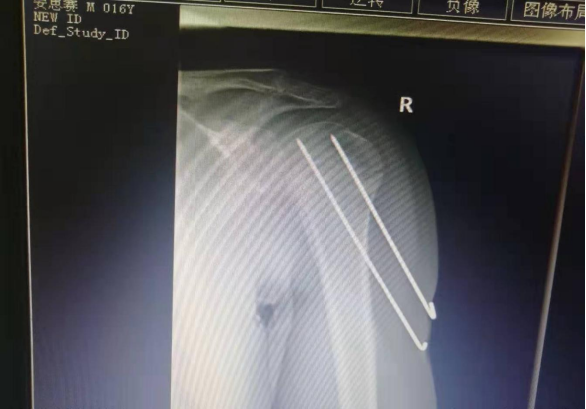

小儿骨科约占住院手术量的3%,包括肱骨髁上骨折闭合或切开复位克氏针内固定术;肱骨近端骨折闭合或切开复位克氏针内固定术;胫骨远端骨折闭合或切开复位克氏针内固定术等。